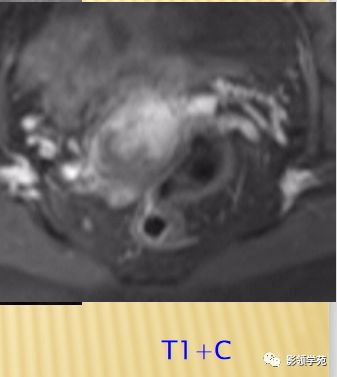

宫颈癌术后复发患者,DWI上病灶较T2 fs及T1+C更加明显